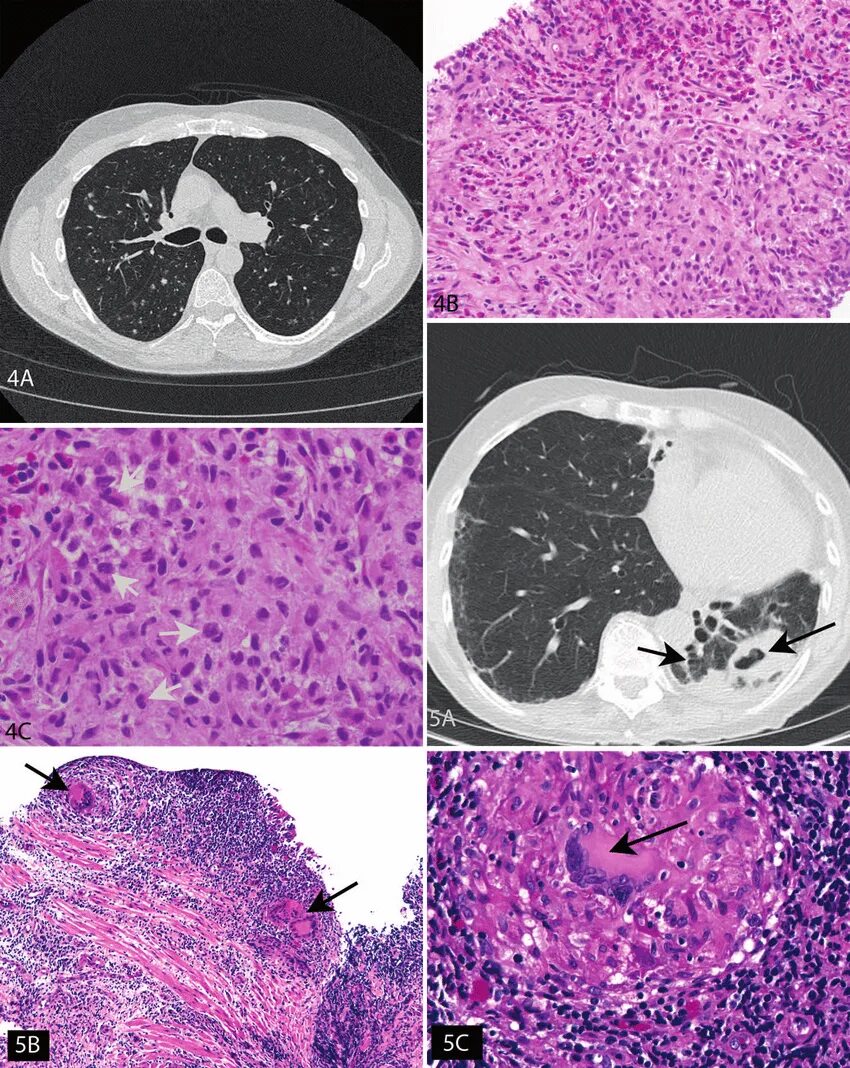

Синусовый гистиоцитоз лимфатического узла